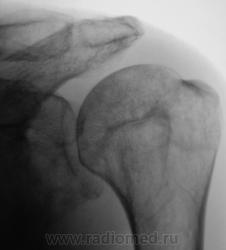

Валентин Львович, а с суставной впадиной лопатки все хорошо? У меня ее структура на подозрении...

Вы совершенно правы Татьяна Валентиновна. Я намеренно "обрезал" снимок, произведенный лаборантами, дабы акцентировать внимание на латеральном угле лопатки. Суставная поверхность лопатки и шейка внушают серьёзные подозрения, и с учетом "пороза" и структуры.